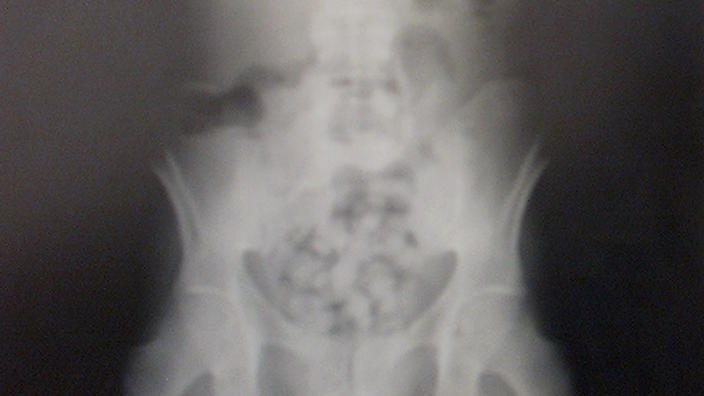

Το περασμένο Σαββατοκύριακο η εντεκάχρονη παραπονέθηκε ότι πονούσε πολύ όταν επέστρεψε στο σπίτι της μητέρας της έπειτα από μια επίσκεψη στο σπίτι του πατέρα της. Διακομίστηκε στα επείγοντα ενός νοσοκομείου. Οι γιατροί ανακάλυψαν μέσα στο σώμα της τις κάψουλες που περιείχαν συνολικά 500 ως 600 γραμμάρια κοκαΐνης.